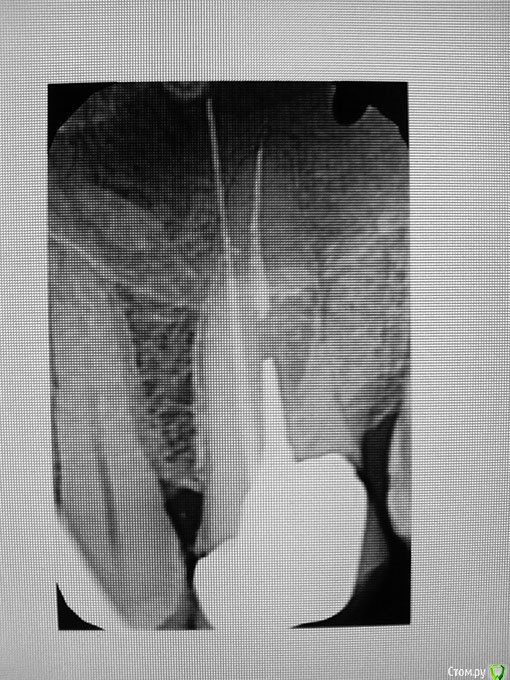

St. Опубликовано 27 июля, 2016 Поделиться Опубликовано 27 июля, 2016 Добрый вечер! У Вас действительно есть несколько сомнительных зубов - шестой слева, о котором Вы говорили, и оба центральных резца верхней челюсти(особенно меня смущает правый).КТ лучше сделать, т.к. оно очень мжет помочь при принятии решения имеет ли смысл перелечивать каналы.Обратите внимание на зубы на предмет кариеса:вверху справа - 7 со стороны 6, 6 под пломбами с обоих сторон, вверху справа - 7 со стороны коронкивнизу слева - 5 со стороны отсутствующего зуба.Зуб мудрости вверху слева нужно удалить.Нижний 7 слева накрыть коронкой.Возможно во время очного осмотра найдутся ещё какие-то вопросы. 1 Ссылка на комментарий

St. Опубликовано 28 июля, 2016 Поделиться Опубликовано 28 июля, 2016 Скажите пожалуйста, это касается только верхней 6-ки слева? Или резцов это тоже касается? И тех, и других. Сегмент не получится сделать, т.к. зубы далеко и в один снимок не влезут. Тем более Вы ещё и имплантацию внизу планируете. Проще делать обе челюсти, чтоб было видно всё. Касательно резцов о чем идет речь, возможно даже удаление понадобится? Скорее всего нет. Вопрос в наличиии воспаления за пределами корня и необходимости перелечивания каналов. 1 Ссылка на комментарий